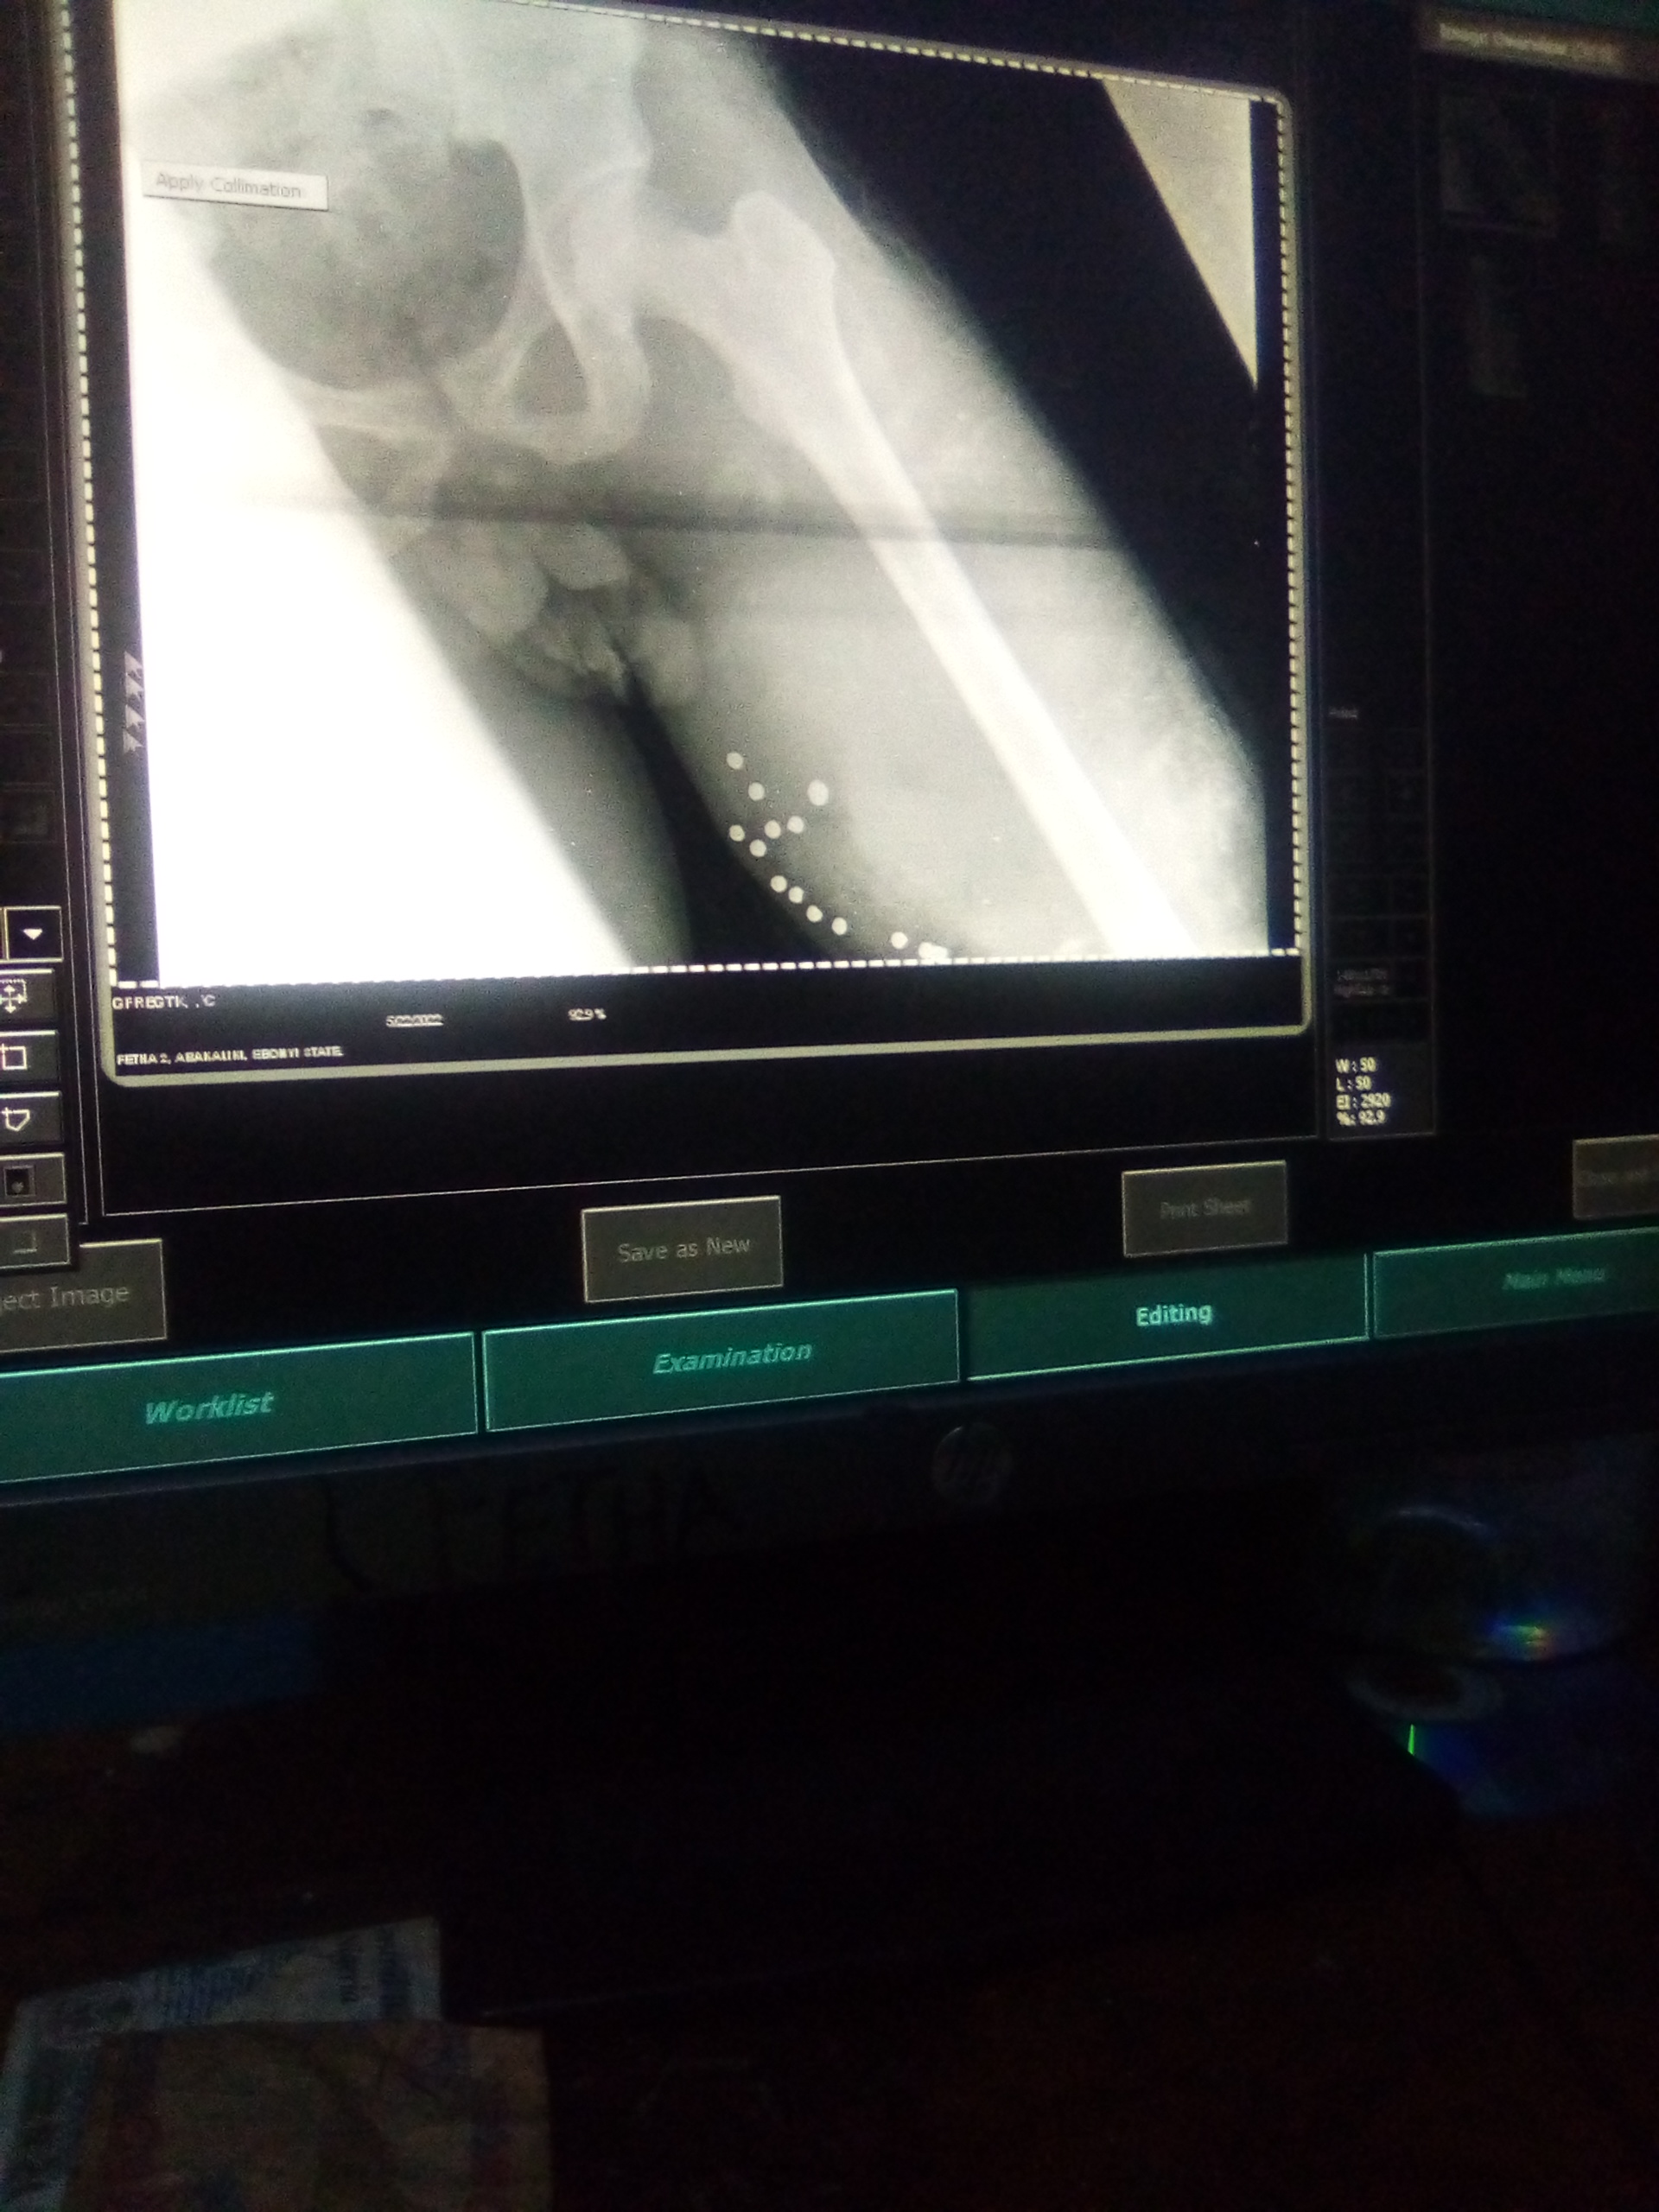

That was an examination carry-out for a patient that had gun shut injury on the femur, that was on Sunday when i was on call duty. The patient was bleeding, profusely, an he was in pain, he had lost a lot of blood, so care need to be taken to minimize pain.

From the above image you can see the bullet, with the aid of the Radiograph, it's will then be easy to remove the bullet through surgical operation on the femur, since there was no fracture of the bone.

After exposure of the patient, i then process the the film, in processing of film to Radiograph, one needs to be careful not to cut off vital area on the Radiograph, after processing, print the film, I ensure i include patient information on the Radiograph for easy identification, then i forward the Radiograph for the radiologist to report it.

So i believe i have passed out a lot knowledge about health, because as human, we all need health care system, from the above image of the patient with gunshot injury, through the Radiograph, it's will be easy to remove the bullet through surgical operation.

From the illustration above you can see that, the patients Radiographers skill to get well again, without the image from X-ray, it will be difficult to remove bullet from the patient with gunshot injury, also in such case, X-ray is important to check if there is a fractured of the bone.